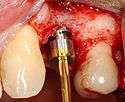

Placing the implant

Most implant systems have five basic steps for placement of each implant:[6](pp214–221)

- Soft tissue reflection: An incision is made over the crest of bone, splitting the thicker attached gingiva roughly in half so that the final implant will have a thick band of tissue around it. The edges of tissue, each referred to as a flap are pushed back to expose the bone. Flapless surgery is an alternate technique, where a small punch of tissue (the diameter of the implant) is removed for implant placement rather than raising flaps.

- Drilling at high speed: After reflecting the soft tissue, and using a surgical guide or stent as necessary, pilot holes are placed with precision drills at highly regulated speed to prevent burning or pressure necrosis of the bone.

- Drilling at low speed: The pilot hole is expanded by using progressively wider drills (typically between three and seven successive drilling steps, depending on implant width and length). Care is taken not to damage the osteoblast or bone cells by overheating. A cooling saline or water spray keeps the temperature low.

- Placement of the implant: The implant screw is placed and can be self-tapping,[18](pp100–102) otherwise the prepared site is tapped with an implant analog. It is then screwed into place with a torque controlled wrench[19] at a precise torque so as not to overload the surrounding bone (overloaded bone can die, a condition called osteonecrosis, which may lead to failure of the implant to fully integrate or bond with the jawbone).

- Tissue adaptation: The gingiva is adapted around the entire implant to provide a thick band of healthy tissue around the healing abutment. In contrast, an implant can be "buried", where the top of the implant is sealed with a cover screw and the tissue is closed to completely cover it. A second procedure would then be required to uncover the implant at a later date.